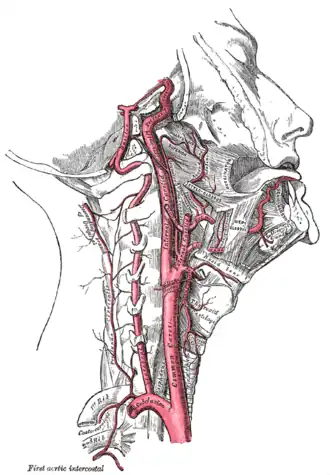

Вну́тренняя со́нная арте́рия (лат. artéria carótis intérna) — парная крупная артерия шеи и головы. Берёт своё начало от бифуркации общей сонной артерии, где последняя делится на неё и наружную сонную артерии[1].

Внутренняя сонная артерия является конечной ветвью общей сонной артерии. Начинается приблизительно с уровня третьего шейного позвонка, где общая сонная артерия разделяется на неё и более поверхностную ветвь — наружную сонную артерию.

Далее внутренняя сонная артерия идёт вертикально вверх и вступает в полость черепа через сонный канал. На протяжении этой части пути она лежит спереди от поперечных отростков первых трёх шейных позвонков (С1—С3). В области сонного треугольника шеи артерия располагается относительно поверхностно. Здесь она лежит позади и кнаружи от наружной сонной артерии, сверху пересекается грудино-ключично-сосцевидной мышцей, и прикрыта глубокой фасцией, платизмой, собственной оболочкой. Далее артерия проходит под околоушной слюнной железой, будучи пересекаемой подъязычным нервом, двубрюшной мышцей, шилоподъязычной мышцей, затылочной артерией и задней ушной артерией. Выше внутренняя сонная артерия отграничивается от наружной сонной артерии посредством шилоязычной и шилоглоточной мышц, верхушкой шиловидного отростка и шилоподъязычной связки, языкоглоточного нерва и глоточных ветвей блуждающего нерва.